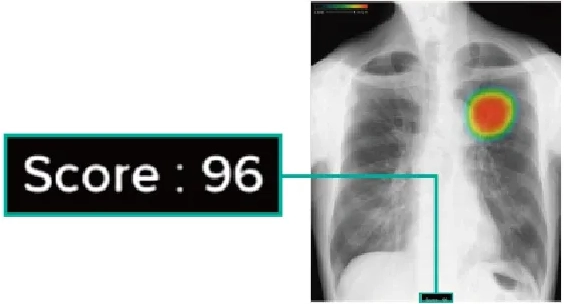

CTは Computed Tomography(コンピュータ断層撮影) の略で、X線を使って体の断面を撮影する装置です。体の内部構造を詳しく画像化できるため、さまざまな病気の発見に役立ちます。近年の技術進歩により、0.5mm間隔で断層画像を撮影できるため、ごく小さな病変も見つけることが可能になりました。また、得られた断面画像を重ね合わせることで、立体的な3D画像を作成することもできます。さらに、必要に応じて 造影剤 を使用すると、腫瘍などの病変部位がより明瞭に写り、周囲の血管の走行や栄養血管の状態を詳しく把握することができます。ただし、造影剤には副作用の可能性があり、また腎機能が著しく低下している場合には使用できないことがあります。造影剤を使うかどうかは、検査内容に応じて医師が判断します。

当院ではGE社製の64列マルチスライスCTを導入しています。被ばく低減可能な逐次近似画像構成法ASiR-VソフトウェアやAI技術を駆使した次世代ワークフローを搭載した最新のCTで検査が行えます。